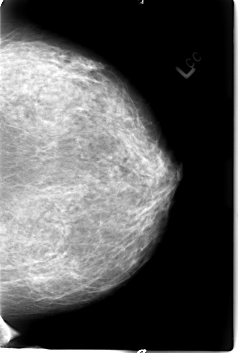

B_3009_1.LEFT_CC

LEFT_CC LINES 4584 PIXELS_PER_LINE 3088 BITS_PER_PIXEL 12 RESOLUTION 50 NON_OVERLAY